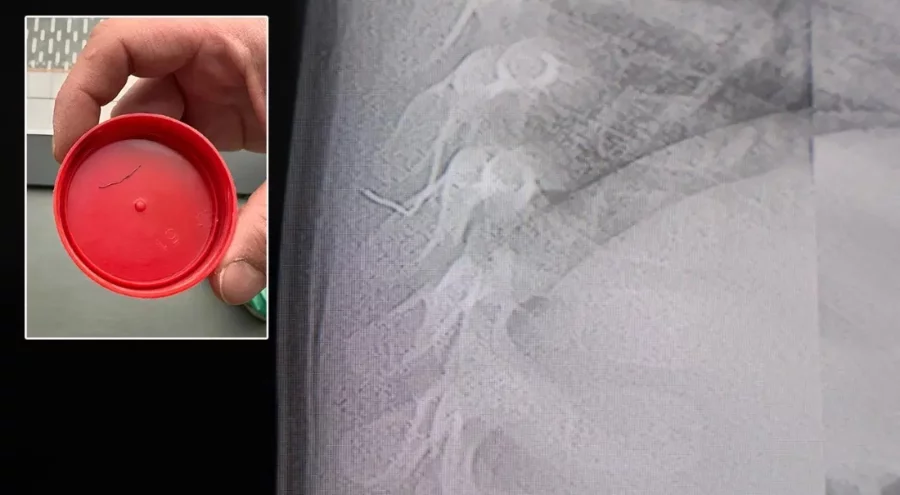

Kahramanmaraş'ta sırt üstü yatmak istemeyen, yatırıldığında ağlama ve huzursuzluğu nedeniyle hastaneye götürülen bir yaşındaki bebeğin sırtından akciğer zarına doğru ilerleyen 2 santimetrelik zımba teli çıktı.

Ailenin başvurduğu hastanede görev yapan Beyin ve Sinir Cerrahisi Uzmanı Prof. Dr. İdris Altun tarafından yapılan tetkiklerde, yabancı cismin cilt altında, omurilik kanalına yakın bir bölgede olduğu ve akciğer zarına doğru ilerlediği belirlendi. Hasta, genel anesteziye alınmadan, lokal anestezi ve sedasyon eşliğinde ameliyata alındı. Yapılan müdahalede yabancı cisim tamamen çıkarıldı. Çıkarılan cismin, ince zımba teline benzer metal bir tel olduğu ve yaklaşık 2 santimetre uzunluğunda bulunduğu tespit edildi. Hasta, aynı gün taburcu edildi.

Konuya ilişkin açıklama yapan Prof. Dr. İdris Altun, "Sırtında yabancı bir cisim olduğu söylenmiş ancak çıkarılamayacağı ve 8 yaşına kadar beklenmesi gerektiği ifade edilmişti. Bize başvurduğunda yaptığımız tetkiklerde, cilt altında, omurilik kanalına çok yakın ve akciğer zarına doğru ilerleyen bir yabancı cisim tespit ettik. Hastamızı tamamen uyutmadan, lokal anestezi ve sedasyon eşliğinde müdahale ederek lezyonu tamamen çıkardık. Çıkardığımız cismin ince zımba teline benzer, yaklaşık 2 santimetre uzunluğunda metal bir tel olduğunu gördük. Bu yabancı cisim alınmasaydı, bölgede enfeksiyon gelişebilirdi. Enfeksiyon sonucu omurilik kanalında ciddi hasarlar oluşabilir, çocuk büyüdükçe cismin hareket etmesine bağlı olarak omurilikte zedelenmeler meydana gelebilirdi. Ayrıca yana doğru ilerleyerek akciğer zarına ve akciğere batma riski vardı. Bu da enfeksiyona ve ilerleyen süreçte tümörle karışabilecek tablolara neden olabilirdi. Şu an hastamız gayet sağlıklı. Gerekli kontrolleri yaptık ve aynı gün taburcu ettik" dedi.